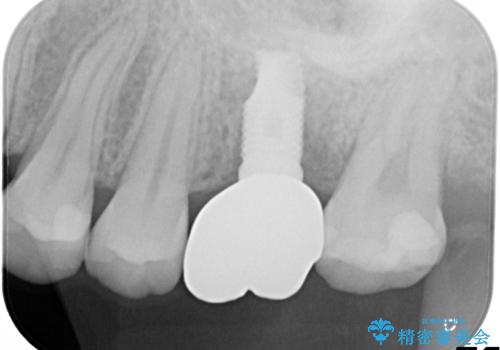

奥歯が割れてしまった! → インプラントによるかみ合わせの回復

- 歯根破折を生じた奥歯を抜歯後、治癒の期間を経てインプラントを埋入

→2時手術の後、インプラントレベルの型どりにて上部構造まで完成させる

インプラントの種類:Zimmer spline

かぶせものの種類:Bellezza